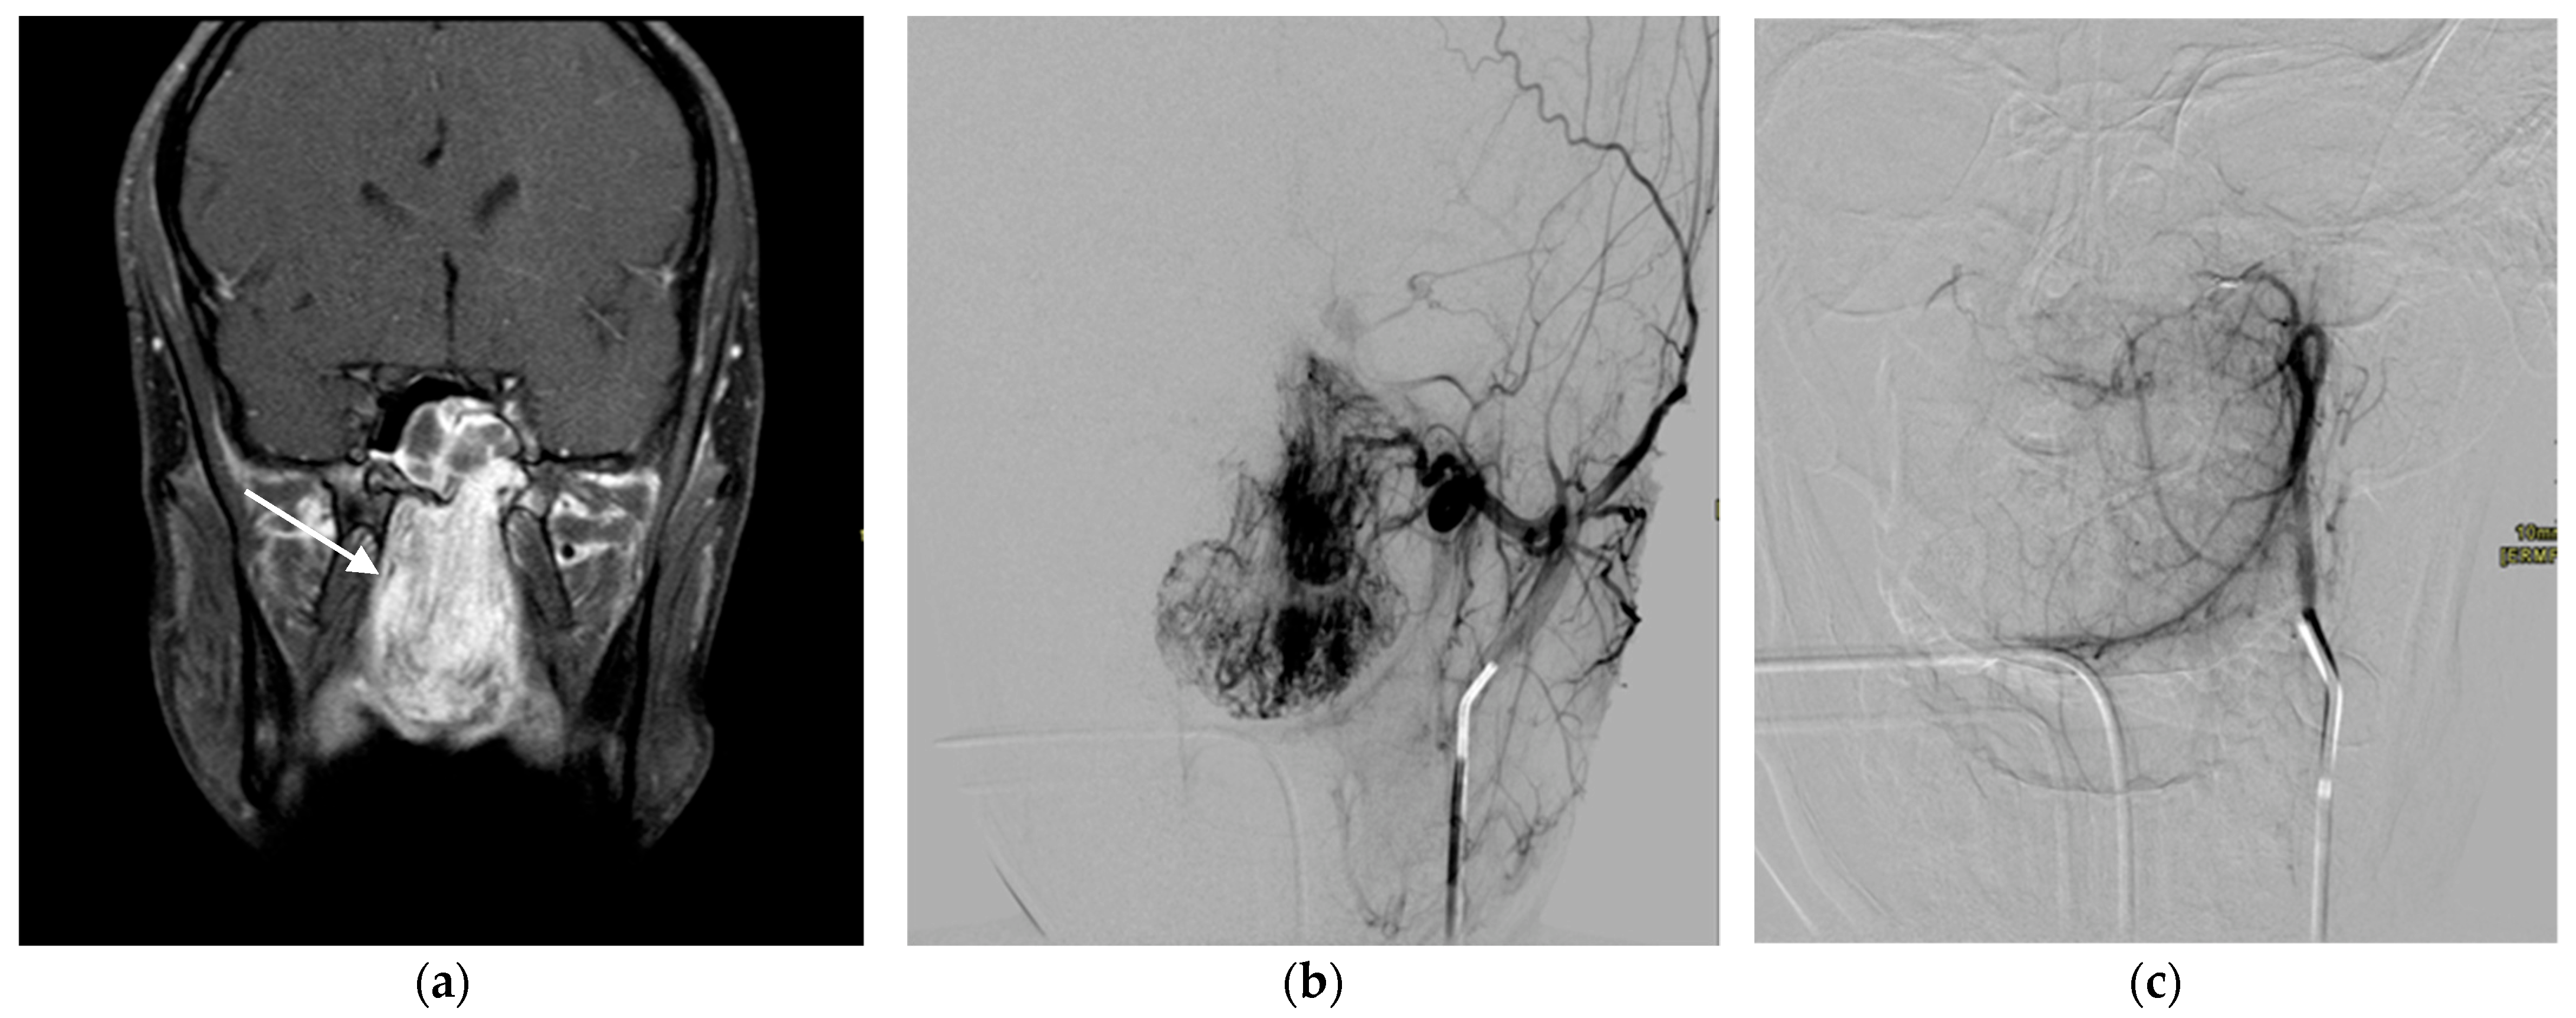

2.1.3. Venous Malformations